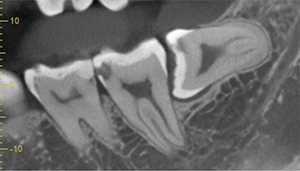

- 抜歯前写真(レントゲン)

- 抜去歯の写真(CT画像)

| 抜歯内容 | 右下の親知らずは横向きに生えて埋まっているため、麻酔をし親知らずの奥に切開を入れて歯ぐきを開き、歯を囲んでいる骨を削り歯の頭部分を割って出してから、残った根の部分を取り出して抜歯は終了しました。 歯ぐきを切った部分は糸で縫っています。このケースでは根の先端が神経に近く麻痺のリスクがありましたが事前にCTを撮影し、神経との位置関係を確認していたため、麻痺が残ることはありませんでした。 約1週間後に糸取りを行い、その際も多少の痛みや腫れはありましたが後日その痛みも無くなりました。 |